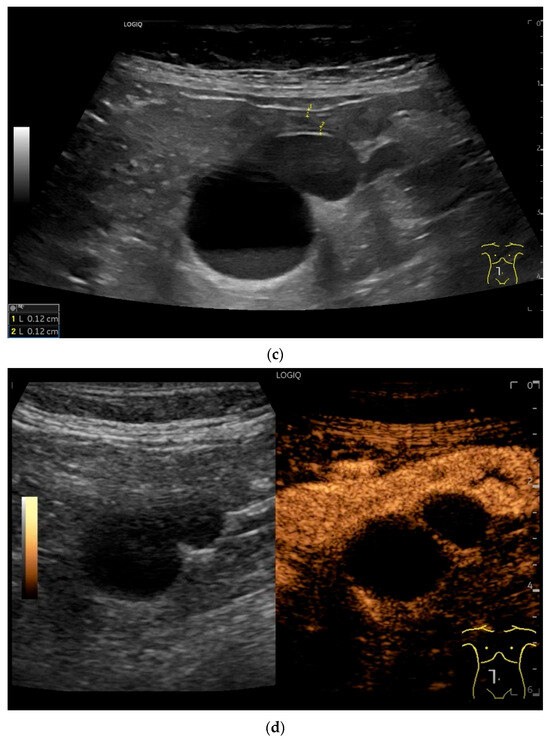

Figure 9.

Burkitt-Lymphoma. In a patient with weight loss, increased abdominal circumference, anemia, and physical weakness, the initial sonographic examination reveals an extensive tumor with intense hypoechogenicity and a connection to the jejunum in the left mid-abdomen. Despite its pronounced hypoechogenicity, a feeding vessel on CDI indicates a solid character (a). The tumor significantly thickens the wall and is intensely hypoechoic. The arrows point to the multisegmental hypoechoic wall thickenings (b). Normal wall structures are still visible (W), and the tumor extends beyond the wall (arrow) (c). In addition to delicate Kerckring folds (KF), there are significantly polypoid thickened KF with pronounced hypoechogenicity (d). The thickening of KF is very extensive (e). Wall thickening was found also in the stomach and colon and allowed endoscopic biopsy to establish the diagnosis.

Figure 10.

Diffuse large B-cell lymphoma (DLBCL). In the right mid-lower abdomen, a large, smoothly circumscribed mass is present around the ileum (“pseudo kidney sign” (a)). Using a high-resolution linear transducer, the mass appears smoothly circumscribed and almost anechoic (b). The ileum runs centrally, and the echogenic wall is clearly defined (c). This wall does not merge into the mass. Since the mass is almost anechoic, it is also difficult in different transducer positions to distinguish whether it is a liquid lesion or a solid mass (b,c). CEUS with 2.4 mL SonoVue (9 MHz linear transducer) shows homogeneous arterial enhancement (d), but the intensity decreases with time in the venous phase (e). The ileal wall enhancement centrally within the mass is more intense than that of the tumor (d,e).

In a study of Hasaballah et al. [113] including 21 patients with small intestine lymphoma (90% DBLCL), marked wall thickening (15.6 ± 5.9 mm) with loss of stratification (76%) and high hypoechogenicity were the typical features of the lymphoma manifestations. In 85.7% the lymphoma was unilocular. Further features were dilatation of the intestinal lumen and periintestinal enlarged lymph nodes. US-guided biopsy was performed in 33% of patients and was successful in 100% [113].

Zhang et al. [115] distinguished the mass type, wall thickening type and non-specific signs in 19 intestine lymphomas. The mass type was characterized by solid and cystic-solid hypoechoic lesions with well-defined margins. Among them were pronounced hypoechoic lesions with dorsal enhanced cancellation. On CDI, abundant blood signals were visible in large masses.

The wall thickening type was characterized by thickening of the bowel walls with hypoechoic (including marked hypoechoic) foci and posterior acoustic enhancement. Nonspecific signs included dilatation of the bowel and enlargement of the mesenteric lymph nodes [115].

Cui et al. [116] described four sonographic patterns on B-mode US in 18 patients with small intestine lymphoma. The majority (61%) were DLBCL. The mass type (66.7%) presented as circumferential, marked intestinal wall thickening. The wall was highly hypoechoic with loss of stratification. The central luminal reflex was hyperechoic. The infiltrative type (5.6%) was a segmental thickening of the bowel wall without visible mass formation with a bowel wall thickness of 2.6 cm in a single case. The mesenteric type (22.2%) was characterized by multiple hyperechoic heterogeneous mesenteric masses with or without involvement of the adjacent bowel wall. The lesion sometimes encapsulated mesenteric vessels without stenosis of the vessel lumen. The mixed type (5.6%) showed a combination of two patterns [116].

On CEUS all small intestine lymphomas showed arterial enhancement (hyperenhancement in 17 of 18 cases) followed by venous washout. Tumor necrosis was observed in 61% of cases, which occurred more frequently in aggressive subtypes than in indolent subtypes. There was no correlation between tumor size and necrosis [116].